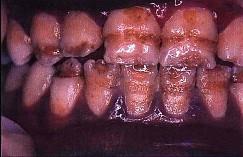

釉质发育不全的临床表现是 ( )

C釉质表面呈深度不等的带状或窝状凹陷